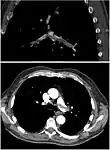

CT pulmonary angiography

CT pulmonary angiography (CTPA) is a pulmonary angiogram obtained using computed tomography (CT) with radiocontrast rather than right heart catheterization. Its advantages are that it is accurate, it is non-invasive, it is more often available, and it may identifying other lung disorders in case there is no pulmonary embolism. The accuracy and non-invasive nature of CTPA also make it advantageous for people who are pregnant.[59]

On CT scan, pulmonary emboli can be classified according to the level along the arterial tree.

On CT scan, pulmonary emboli can be classified according to the level along the arterial tree. Segmental and subsegmental pulmonary emboli on both sides

Segmental and subsegmental pulmonary emboli on both sides CT pulmonary angiography showing a "saddle embolus" at the bifurcation of the main pulmonary artery and thrombus burden in the lobar arteries on both sides.

Assessing the accuracy of CT pulmonary angiography is hindered by the rapid changes in the number of rows of detectors available in multidetector CT (MDCT) machines.[60] According to a cohort study, single-slice spiral CT may help diagnose detection among people with suspected pulmonary embolism.[61] In this study, the sensitivity was 69% and specificity was 84%. In this study which had a prevalence of detection was 32%, the positive predictive value of 67.0% and negative predictive value of 85.2%. However, this study's results may be biased due to possible incorporation bias, since the CT scan was the final diagnostic tool in people with pulmonary embolism. The authors noted that a negative single slice CT scan is insufficient to rule out pulmonary embolism on its own. A separate study with a mixture of 4 slice and 16 slice scanners reported a sensitivity of 83% and a specificity of 96%, which means that it is a good test for ruling out a pulmonary embolism if it is not seen on imaging and that it is very good at confirming a pulmonary embolism is present if it is seen. This study noted that additional testing is necessary when the clinical probability is inconsistent with the imaging results.[62] CTPA is non-inferior to VQ scanning, and identifies more emboli (without necessarily improving the outcome) compared to VQ scanning.[63]